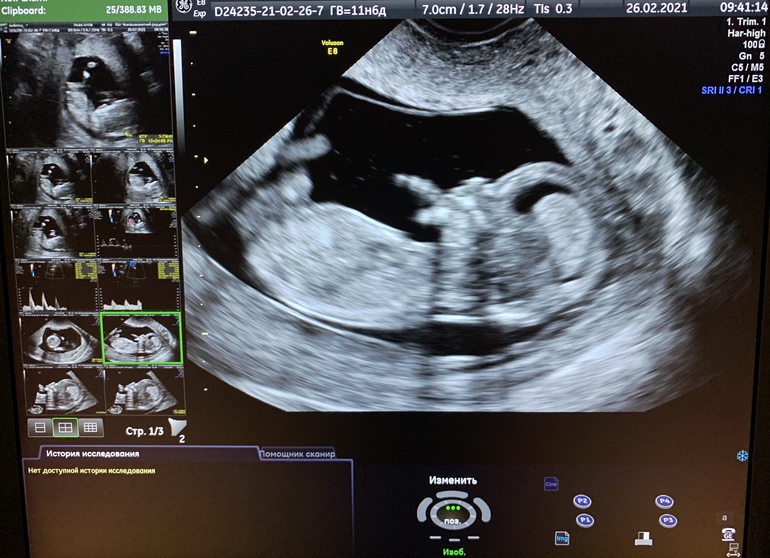

Первый скрининг пройден

Ну вот и я прошла 1 скрининг. В начале Б безумно боялась этого исследования, а после последнего УЗИ меня отпустило и в итоге шла спокойная как удав, сама себе удивилась.

По УЗИ с малышом все хорошо, все показатели в норме. Осталось дождаться результатов крови. Во время исследования малыш немного крутился и шевелил ручками, милота невозможная. Настоящий человечище там, не смотря на свои почти 6см КТР.

Срок по М 11+6. По УЗИ раньше опережали на 2 дня, а на скрининге получилось еще +2 дня.